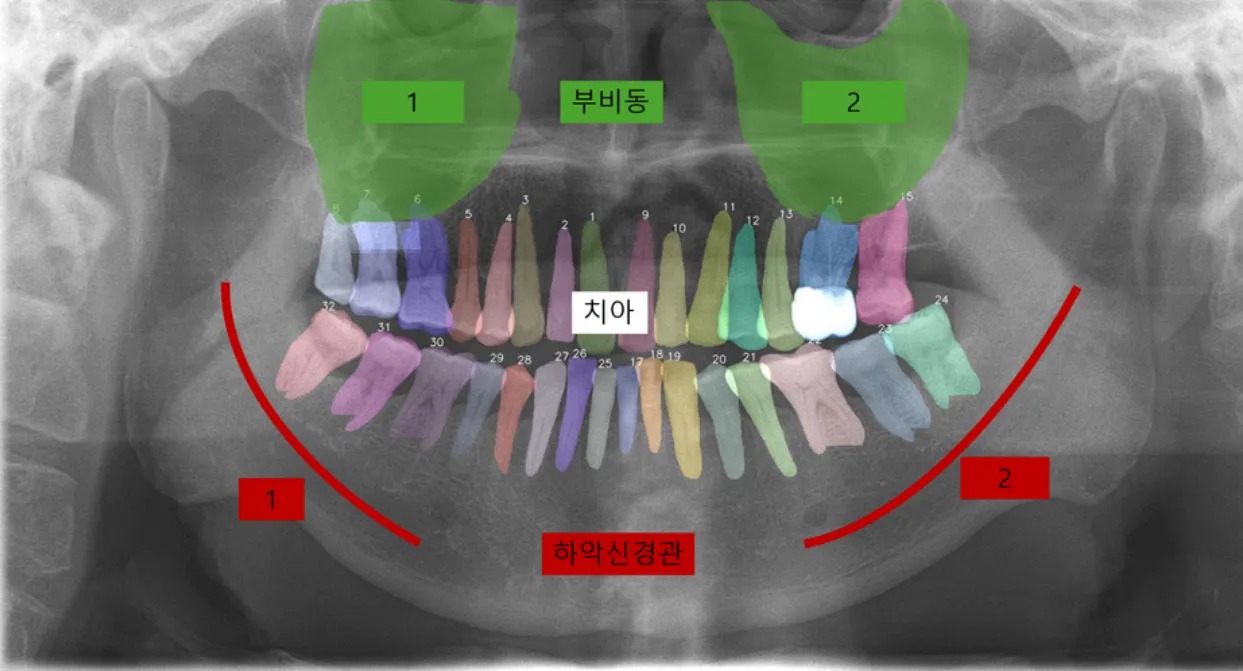

This project focused on customizing the Segment Anything Model (SAM) and enhancing its performance for dental panoramic X-ray segmentation. We combined LoRA-based fine-tuning with an iterative prompt refinement strategy, and also developed user-friendly labeling tool features to improve both segmentation accuracy and clinical usability.

Dentists often face difficulties identifying subtle lesions in panoramic X-rays. However, the available dataset was limited (~2,000 images) and of inconsistent quality, leading to segmentation errors and unreliable training. To overcome this, we designed a dual approach:

Root segmentation improvement in low-quality and boundary-ambiguous environments